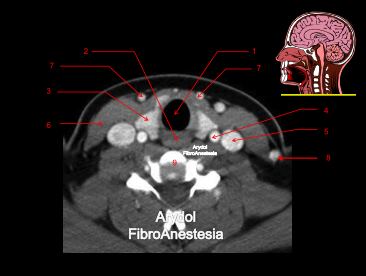

CORTE A NIVEL DE LA GLOTIS

1.comisura anterior; 2.cuerda vocal; 3.aritenoides; 4.cartílago tiroides; 5.cartílago cricoides; 6.comisura posterior; 7.hipofaringe-boca esofágica; 8.glotis (espacio glótico); 9.arteria carótida común; 10.vena yugular interna; 11.músculo esternocleidomastoideo; 12.vértebra